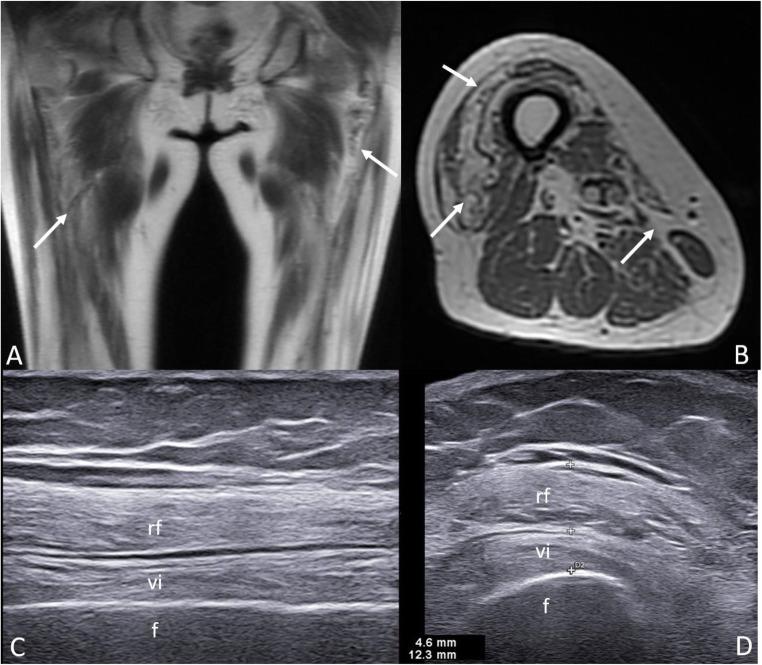

Ultrasound (US) and magnetic resonance imaging (MRI) are accurate and sensitive in the assessment of inflammation and structural damage at the joint and soft tissue structures in patients with SLE. The US is particularly helpful for the detection of joint and/or tendon inflammation in patients with arthralgia but without clinical synovitis, and for the early identification of bone erosions. MRI plays a key role in the early diagnosis of osteonecrosis and in the assessment of muscle involvement (i.e., myositis and myopathy). Conventional radiography (CR) remains the traditional gold standard for the evaluation of structural damage in patients with joint involvement, and for the study of bone pathology. The diagnostic value of CR is affected by the poor sensitivity in demonstrating early structural changes at joint and soft tissue level. Computed tomography allows a detailed evaluation of bone damage. However, the inability to distinguish different soft tissues and the need for ionizing radiation limit its use to selected clinical circumstances. Nuclear imaging techniques are valuable resources in patients with suspected bone infection (i.e., osteomyelitis), especially when MRI is contraindicated. Finally, dual energy X-ray absorptiometry represents the imaging mainstay for the assessment and monitoring of bone status in patients with or at-risk of osteoporosis. Imaging provides relevant and valuable information in the assessment of MSK involvement in SLE.

超声(US)和磁共振成像(MRI)在评估 SLE 患者关节和软组织结构的炎症和结构损伤方面具有准确性和敏感性。US 特别有助于检测有关节痛但无临床滑膜炎的患者的关节和/或肌腱炎症,并有助于早期识别骨侵蚀。MRI 在早期诊断骨坏死和评估肌肉受累(即肌炎和肌病)方面发挥着关键作用。传统射线照相(CR)仍然是评估关节受累患者结构损伤和骨骼病理学的传统金标准。CR 的诊断价值受到在关节和软组织水平上显示早期结构变化的敏感性差的影响。计算机断层扫描允许对骨损伤进行详细评估。然而,由于无法区分不同的软组织以及需要电离辐射,其在选择的临床情况下限制使用。核成像技术是怀疑骨骼感染(即骨髓炎)患者的有价值的资源,尤其是在 MRI 禁忌的情况下。最后,双能 X 射线吸收法是评估和监测骨质疏松症或有骨质疏松症风险的患者骨骼状况的影像学主要方法。影像学在评估 SLE 的 MSK 受累方面提供了相关和有价值的信息。